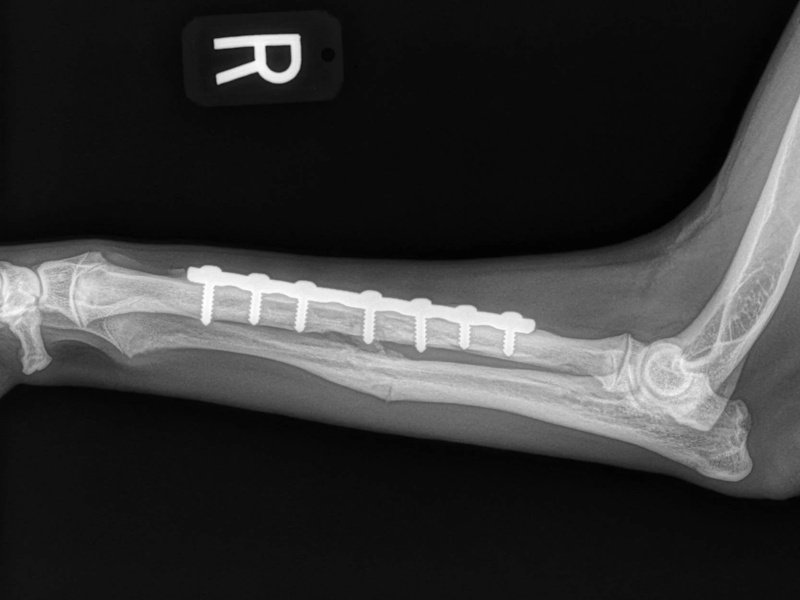

An osteotomy is a surgical cut in a bone. In the cruciate deficient stifle, a cut is made in the top of the tibia. The top portion of bone that contains the articular surface is rotated to level it. The two pieces of bone are held in place with a metal plate and screws.

Post Surgical Radiographs

While the patient is still anesthetized, the patient is taken into radiology for post-surgery radiographs (X-rays). The radiographs are assessed to measure the new tibial plateau angle. We are aiming for 5-6 degrees relative to the long axis of the tibia. The apparatus (plate and screws) are assessed for size and appropriate position.

Fore Limb (Humerus, Radius/Ulnar, Metacarpus)

Hind Limb (Pelvis, Femur, Patella, Tibia/Fibula, Lateral Malleolus)